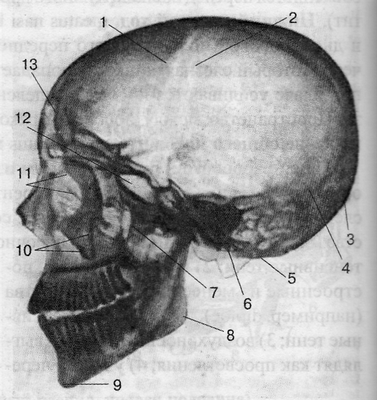

Для изучения костей черепа применяют традиционные проекции: прямую, боковую, а также аксиальные (косые) и специальные укладки (рис. 3.31 и 3.32). Для определения формы черепа на рентгенограммах измеряют фронтальный, сагиттальный и вертикальный размеры.

Вертикальный размер (высота черепа) определяется по перпендикуляру, проведенному от наружного слухового прохода до внутренней пластинки теменной кости. Сагиттальный и вертикальный размеры измеряются на рентгенограммах, выполненных в боковой проекции.

На рентгенограмме черепа в прямой проекциипрежде всего необходимо обратить внимание на структуры, формирующие глазницы, полость носа, анатомические образования в области верхней челюсти, оцениваются форма, размеры и характер лобной и верхнечелюстной пазух, а также большое затылочное отверстие. На рентгенограмме в боковой проекцииможно оценить черепные ямки, толщину и рельеф костей мозгового черепа. Особое внимание необходимо обратить на размеры и форму турецкого седла, клиновидной и лобной пазух.Оценка формы и размеров турецкого седла позволяет судить о его содержимом - гипофизе.

Рис. 3.32. Рентгенограмма черепа взрослого человека; боковая проекция.

1 - os frontale; 2 - sut. coronalis; 3 - protuberantia occipitalis externa; 4 - sut. Lambdoidea; 5 - processus mastoideus; 6 - condylus occipitalis; 7 - fossa pterygopalatina; 8 - angulus mandibulae; 9 - protuberantia mentalis; 10 - processus zygomaticus maxillae; 11 - labyrinthus ossis ethmoidalis; 12 - sinus sphenoidalis; 13 - sinus frontalis.